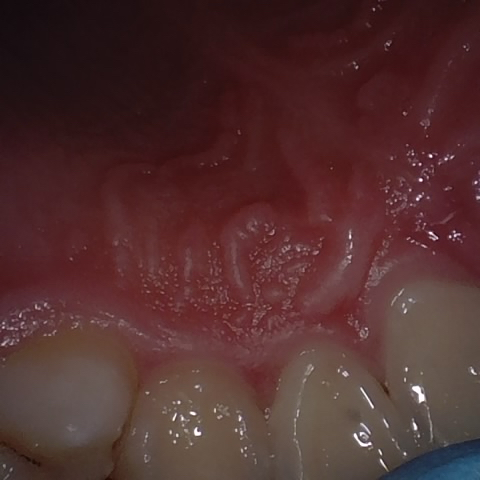

NHD39990

Annotated as "Good"